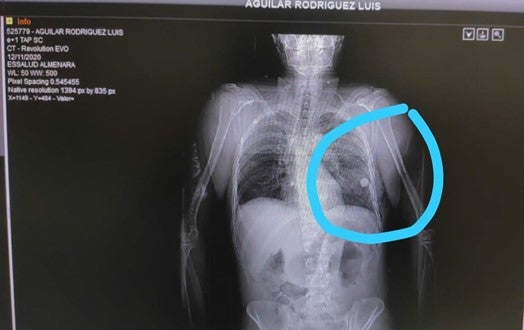

Radiografía que muestra una canica alojada en el pulmón de Luis Aguilar Rodríguez.

Fotografía proporcionada por la familia de Luis Aguilar Rodríguez.